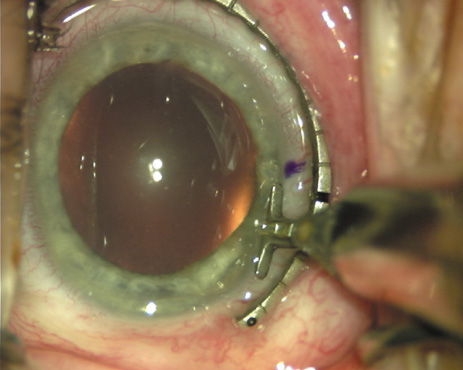

Case 1 is a 68-year-old male who presented for right cataract surgery. His refraction was −1.00 +2.25 × 80 and was recorded as reliable, consistent with his modest cataract density. Keratometry readings were 44.75 × 75 and 43.00 × 165. Corneal topography confirmed slightly more than 2.00 D of regular and slightly oblique cylinder. Consulting the nomogram, a plan was devised for a pair of LRIs to be centered over the 75-degree axis, with each incision delineating 45 degrees of arc. A single plane phaco incision was used and maintained at a size of less than 3.2 mm (Figs. 811).

Fig. 8. Steep meridian is confirmed intraoperatively by keratoscopy. In this left eye viewed from the temporal side, the “short axis” of the corneal mire is seen to be at the 75-degree meridian. (Reprinted from Hardten DR, Lindstrom RL, Davis EA. Phakic Intraocular Lenses: Principles and Practice. Thorofare, NJ: SLACK Incorporated, 2004, with permission.)